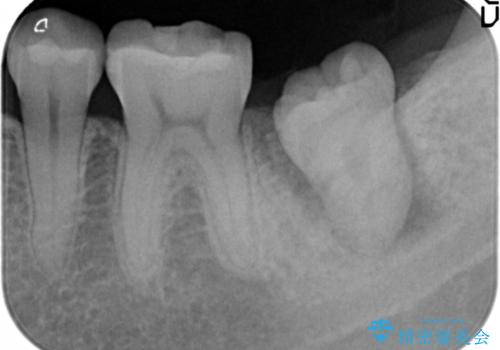

精査したところ、左下の奥歯にはひびが入っていて、保存不可能な状態でした。

義歯・インプラント・親知らずの移植の選択肢を提案したところ、移植をご希望されました。

割れている奥歯を抜去後左上の機能していない親知らずを移植し、生着したのち根管治療・補綴を行いました。

インプラントや義歯を用いることなく咬合を回復することができ、喜んで頂けました。

治療期間も抜歯後3ヶ月以内かつ少ない来院回数(初診含めて6回)で治療を終えることができ、ご満足頂けました。